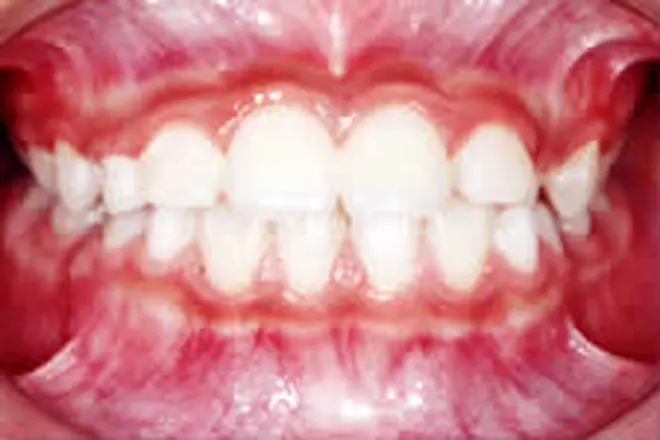

子どもの矯正 治療例2

まだ乳歯が多く残っていて、全体的な矯正治療はできません。そこで裏側に舌突出防止装置を付け、舌癖を改善して開咬を治療しました。

開咬が解消され、口をあけたときに前歯の隙間が出なくなりました。

| 患者さまの年齢・性別 | 9歳・女性 |

| 治療期間 | 1年 |

| 治療費(税込) | 165,000円 |

| 主訴 | 前歯で噛めない |

| 診断名・主な症状 | 開咬 |

| 治療に用いた主な装置 | 舌突出防止装置 |

| 治療内容 | 舌側に舌突出防止装置を付けることで、舌が前歯を押すのを防ぎます。 |

| 抜歯部位 | 非抜歯 |